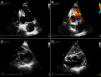

Este doente apresentava, desde a admissão, eletrocardiograma com onda Q patológica e onda T negativa em III e aVF, sugerindo cicatriz inferior. O ecocardiograma transtorácico mostrou deformação da parede inferior, com expansão em sístole, aparente perda de espessura da parede, associado a derrame pericárdico ligeiro, sugerindo pseudoaneurisma versus aneurisma verdadeiro (Figura 1).

Ecocardiograma transtorácico sugestivo de pseudoaneurisma da parede inferior (seta). Em apical duas câmaras visualização de aneurisma da parede inferior com redução da espessura da parede e Doppler‐cor sugerindo fluxo ventrículo‐aneurisma (A e B); imagem do pseudoaneurisma em corte transversal‐paraestenal curto‐eixo no plano basal (C) e em janela subcostal (D); derrame pericárdico ligeiro (*).